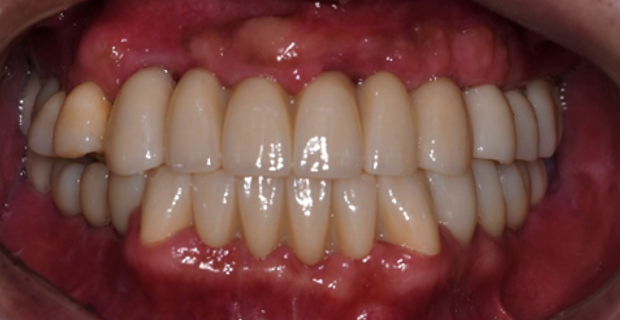

치료 후

전체 치아를 발치하지 않고 보존하여 쓸 수 있는 오른쪽 위 작은 어금니들과 아래쪽 송곳니들을 살려 전체 치아 치료를 해 드렸습니다.

수직고경도 회복하여 심미적으로도 우수하게 좋아졌습니다.